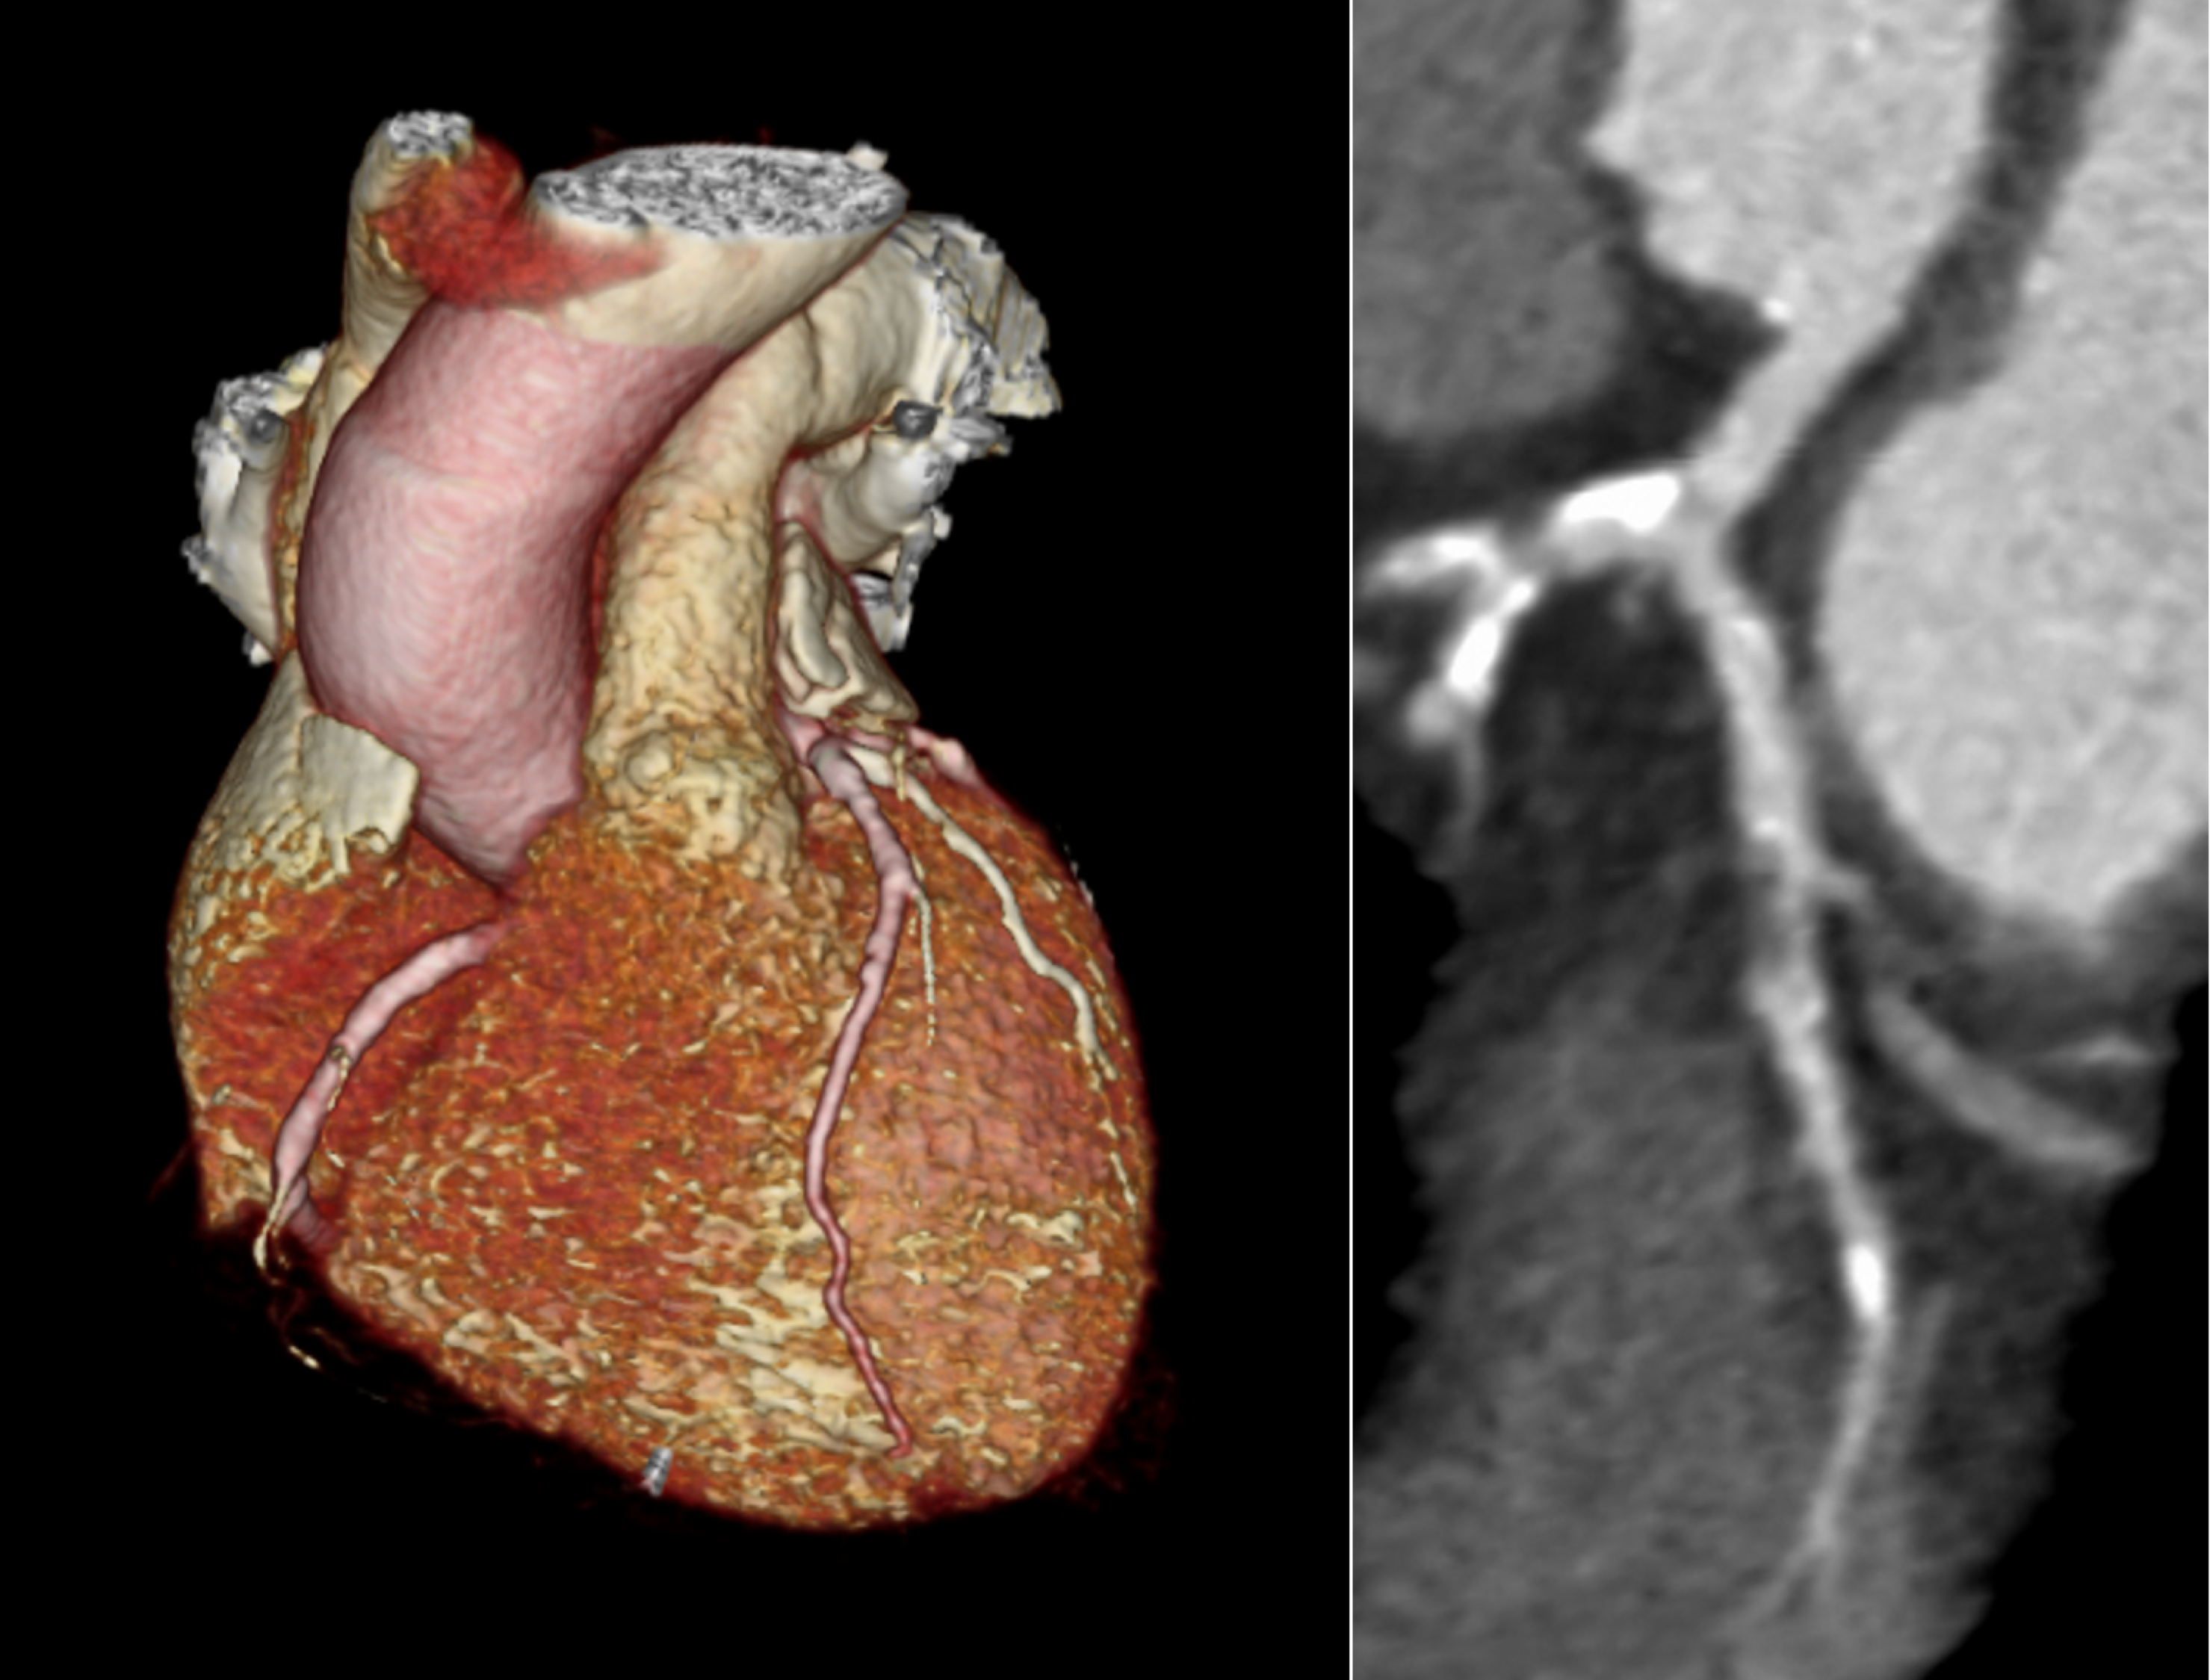

(Left) CTA plaque analysis showing lumen in blue, noncalcified plaque in red and low-attenuation plaque (LAP) in orange. (Right) LAP increases as the calcium score increases but is common in symptomatic patients with zero or low calcium score. All images courtesy of SCOT-HEART trial."Quantitative assessment of coronary artery plaque provides the most robust and comprehensive assessment of plaque subtypes throughout the coronary artery tree. In particular, we were able to assess the highest risk plaque sub-type, the low-attenuation noncalcified plaque," she added.